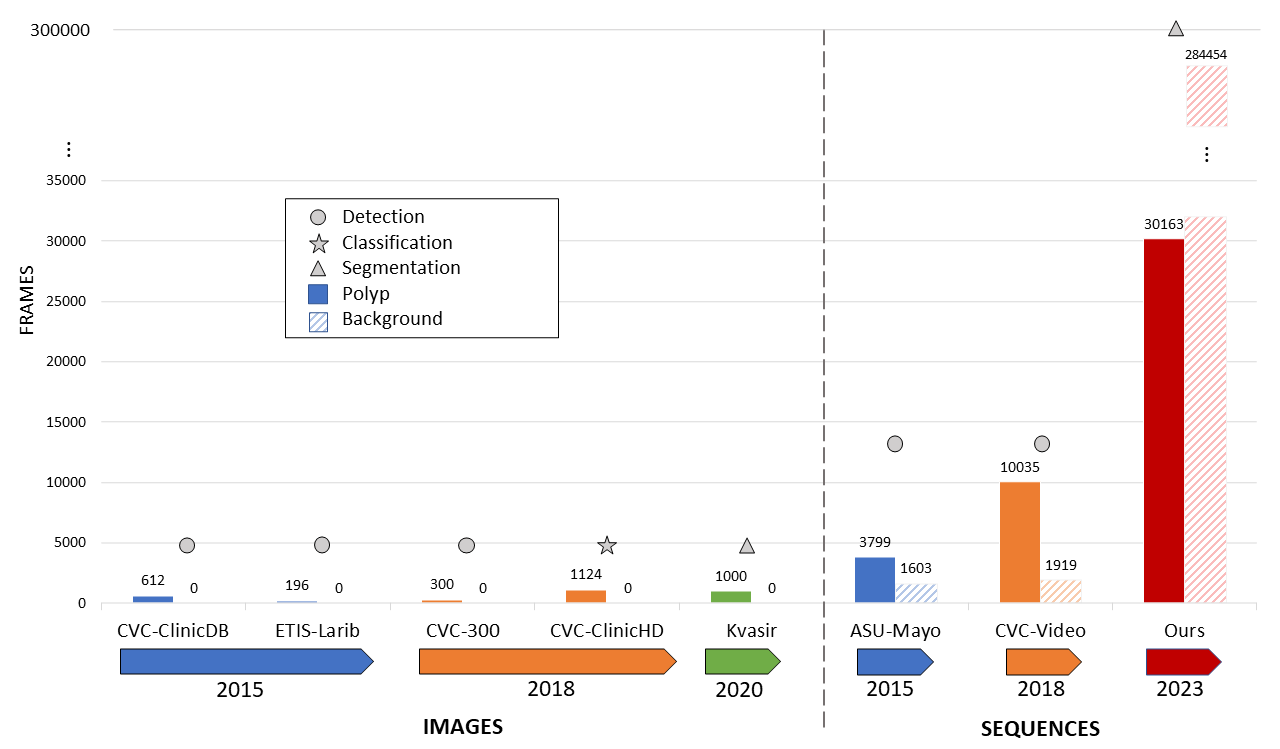

Nowadays, there exist multiple open datasets that include polyp observations from colonoscopies, allowing the design, implementation, and adjustment of computational representations to support several polyp characterization tasks. For instance, the first available datasets were the CVC-Clinic DB111https://polyp.grand-challenge.org/CVCClinicDB/ (612 polyp frames with respective masks from 31 colonoscopies) and the ETIS-Larib 222https://polyp.grand-challenge.org/Databases/ (196 polyp frames with respective ground truth masks from 34 colonoscopies). These datasets were designed for polyp detection tasks, allowing to development of methods dedicated to model polyp shape features [10, 11]. Around this data, several analyses were proposed to capture non-linear polyp-background features from receptive field blocks (dilated convolutions enhance local representations) [4, 16].

Also, the CVC-300 database 333http://adas.cvc.uab.es/endoscene was publicly available to bring images of polyps with additional morphological variability (flat and peduncular). This database consists of 300 annotated polyp images extracted from 15 different videos [12]. Besides, the CVC-ClinicHD dataset (composed by more than 1100 HD images showing a polyp) was an effort to bring colonoscopy data with major descriptions about polyp malignancy classes 444https://giana.grand-challenge.org/Home/. These improved datasets open new polyp-related challenges not only related to size, and morphology but also surface patterns to address biopsy estimations [17, 18]. More recently, the Kvasir-SEG database, composed of 1450 annotated polyp frames was published in 2020 for polyp segmentation task 555https://datasets.simula.no/kvasir-seg/. This open-access dataset brings new computer-aid diagnosis systems around the segmentation, detection, and localization of polyps [19].

Short colonoscopy sequences were also added to propose challenges in close realistic scenarios that include intestinal background, i.e, frames without polyps. For instance, the ASU-Mayo database, published in the Automatic Polyp Detection challenge in 2015 666https://polyp.grand-challenge.org/AsuMayo/, contains for training purposes, 20 short colonoscopy sequences (one minute on average) balanced between records with polyp and only intestinal folds. Regarding the test split, this dataset has 18 videos without public ground truth annotations. In the same line, the CVC-Video, published in the Endoscopic Vision Challenge in 2018 777https://giana.grand-challenge.org/, is composed of 18 short colonoscopy sequences for training and test (one minute on average) with polyps/non-polyps and the corresponding binary ground truth annotation. Around these more realistic scenarios, several computational techniques that include deep representations and state-of-the-art techniques, have been proposed to address the polyp characterization [4, 16].

This work presents the COLON dataset, which collects the major number of polyp and non-polyp frame observations. Regarding the current open dataset in the state-of-the-art, this dataset includes recovered samples extracted from 30 colonoscopy video sequences with polyps, from typical procedures with a huge amount of intestinal background frames together with polyp findings with high visual and shape variability. Figure 1 reports a comparison between the proposed dataset and the baseline datasets introduced in the state-of-the-art. As observed, the proposed dataset exceeds the amount of available data, and the labeled information, introducing the task of polyp segmentation task in long sequences and allowing approximate strategies to real scenarios.